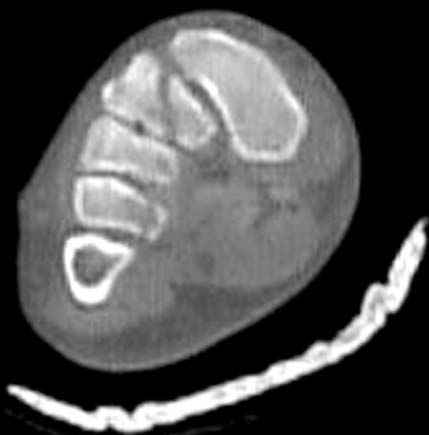

Вложение не в текстовом формате было извлечено…

Имя     : CT 3.jpg

Тип     : image/jpeg

Размер  : 21988 байтов

Описание: отсутствует

Url     : http://weborto.net:8080/pipermail/ortho/attachments/20080320/e19da97a/attachment-0005.jpg